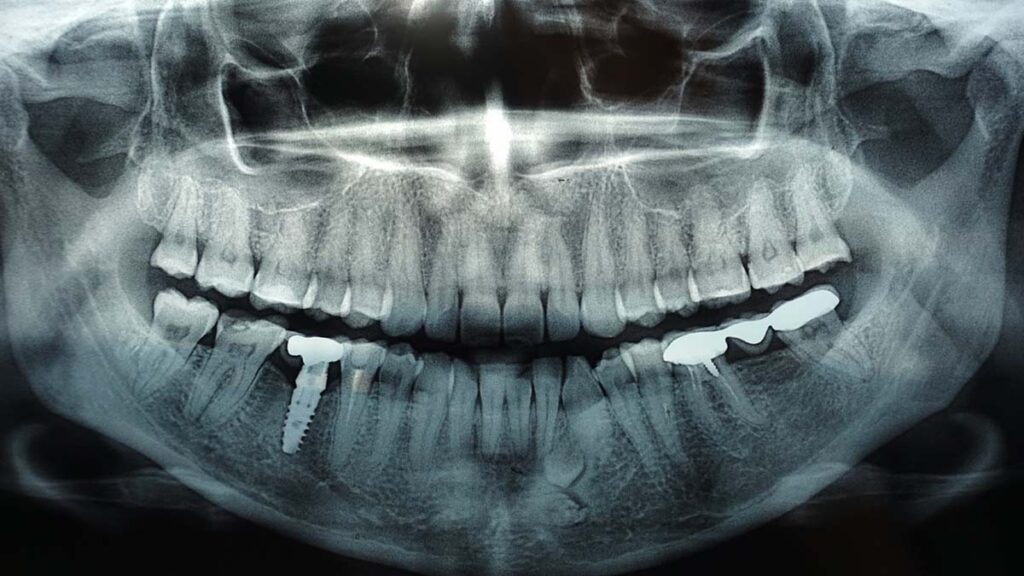

- Panoramic X-rays: These provide a broad view of the entire mouth, including the jaw, teeth, and sinuses. They are particularly useful for treatment planning and assessing the positioning of wisdom teeth.

- Prevention of Complications: For patients with dental restorations (such as crowns, fillings, or implants), X-rays are used to monitor the integrity of these treatments. Regular X-rays help ensure that restorations remain effective and don’t cause future complications.